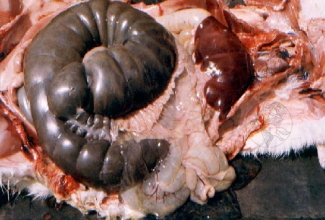

Fotodel on näha küüliku sooles kinni jäänud väljaheiteid